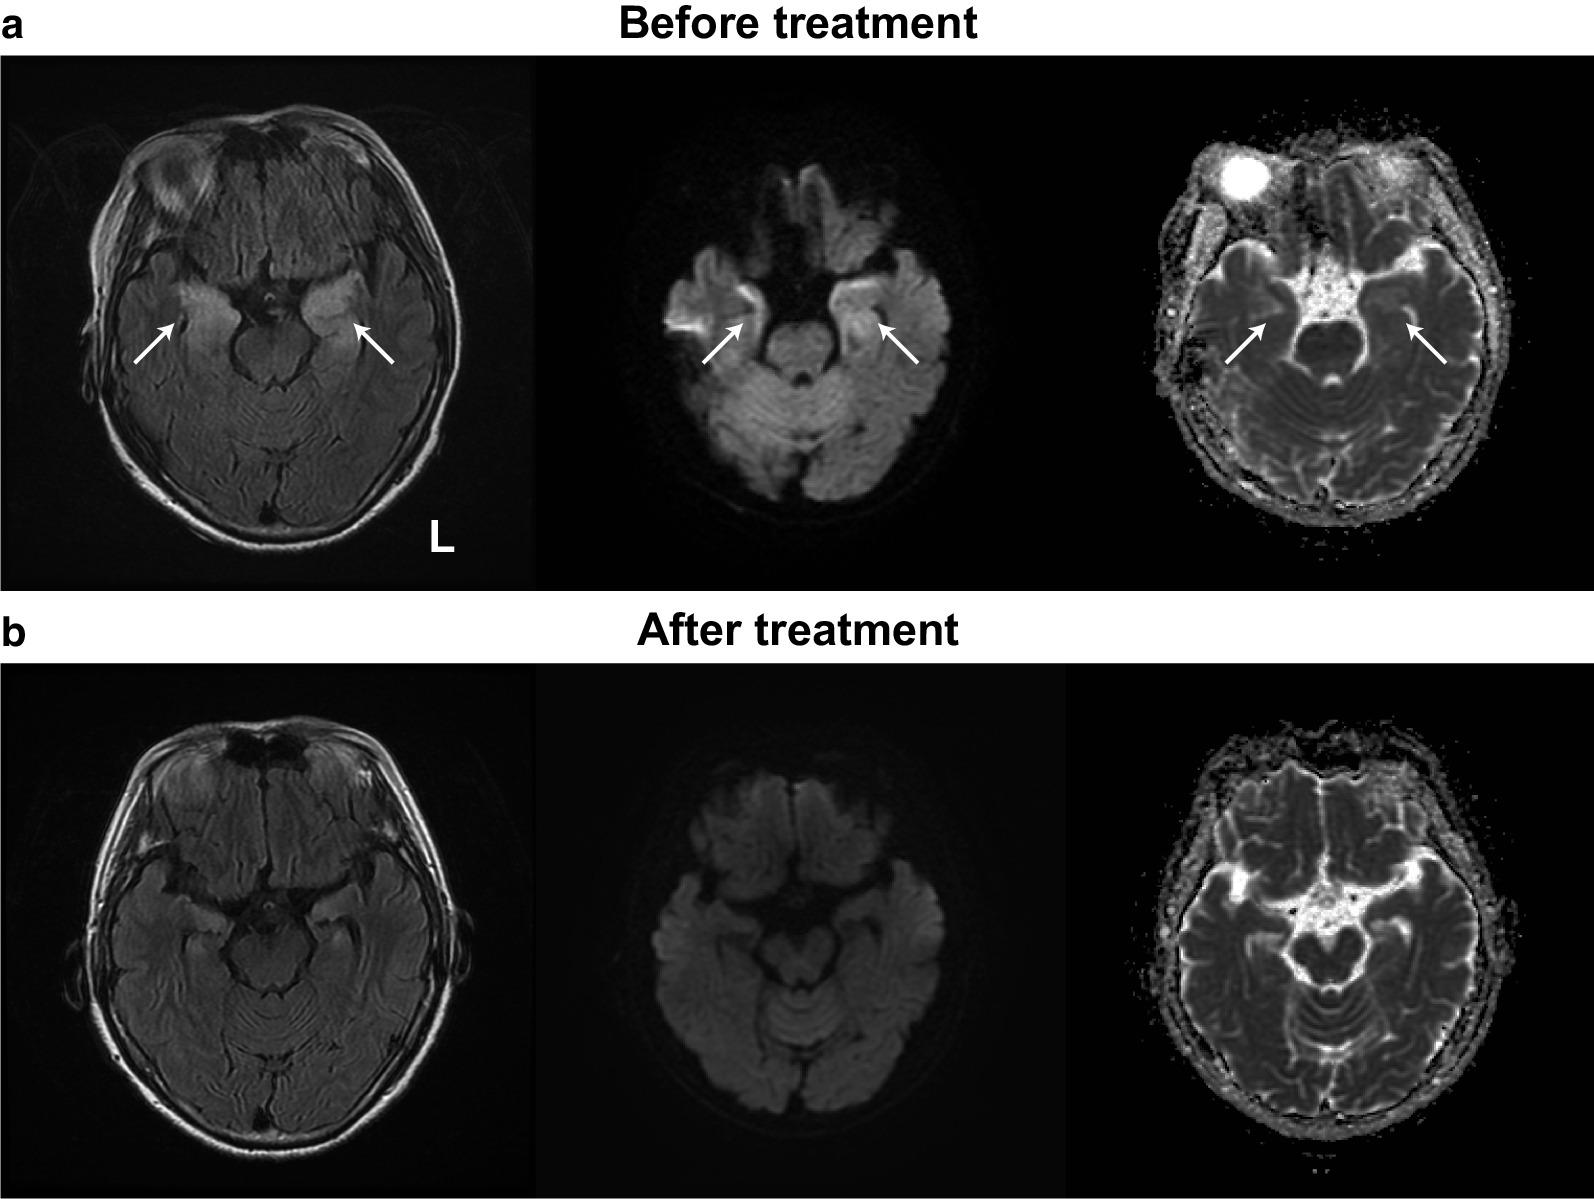

一名 68 岁日本女性因意识障碍就诊于我院急诊科。入院时,患者存在低氧血症。左心室造影显示左心室中部无运动,心尖部和底部运动亢进,诊断为中间段 Takotsubo 综合征。然而,在意识障碍和 Takotsubo 综合征症状改善后,她的哥哥在探视时注意到她的行为有些异常。随后,我们在入院后 1 周请神经内科会诊。其哥哥回忆起患者在发病前几天(如在其居住的大楼错误进入其他住户的房间或他人的汽车内)曾出现过异常行为,提示有地点定向障碍。脑磁共振成像显示内侧颞叶信号增强,在液体衰减反转恢复序列上最为明显;此外,脑脊液分析显示轻度淋巴细胞增多。最终,我们诊断为中间段 Takotsubo 综合征伴自身免疫性边缘性脑炎。